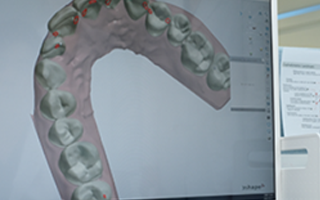

• iTero Lumina 3D 구강스캔

힘든 본뜨기 과정 없이 최신 iTero Lumina 구강스캐너로

치아와 잇몸을 고해상도로 스캔할 수 있으며,

크기가 작아 어린 환자도 편안하게 사용할 수 있습니다.

또한 교정 후 모습을 시뮬레이션해 정밀한 치료 계획이 가능합니다.